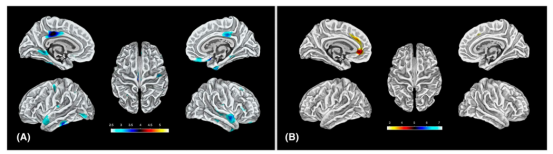

SBM三维伪彩色映射。(A)婴儿痉挛症(IS)< 健康对照(HC)。显示IS组皮层分形维度减小区域:双侧后扣带回、右侧胼胝下回、双侧颞下回、右侧颞中回、左侧枕叶楔回、右侧中央后回(p<0.001,k>30)。(B)IS > HC。显示IS组皮层分形维增加区域:左侧前扣带回(p<0.001,k>30)。